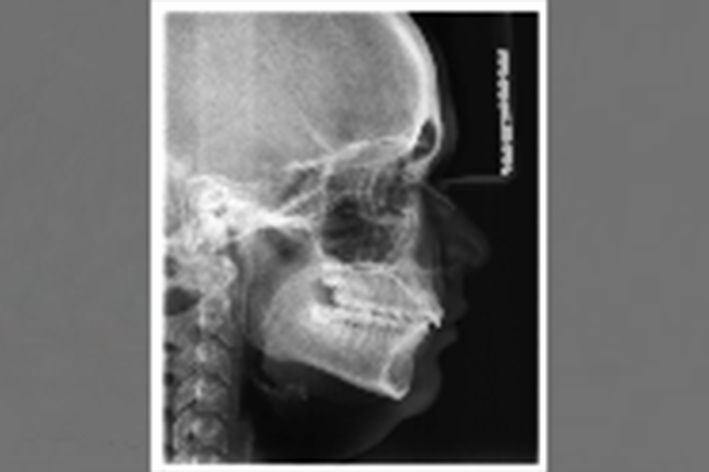

FRS

Abkürzung für Fernröntgenseitenaufnahme. Es handelt sich um eine Röntgenaufnahme des gesamten Schädels, deren anschließende Vermessung diagnostische Hinweise auf das Wachstumsmuster und die Lage der Kiefer zueinander gibt.